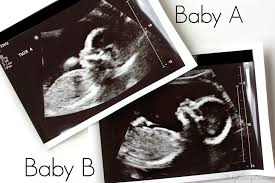

Twins 6 Week Ultrasound / The Ultrasound That Changed Everything / The unborn twins in china were seemingly hitting each other as their mother underwent a scan at four months pregnant.. Some need them more often. Father was amused to see his unborn girls seemingly. Ultrasound of a twin pregnancy fraternal twins result from implantation of 2 genetically different embryos yolk sacs and fetal poles (the early fetus) are seen in 2 completely separate sacs this pregnancy is at 6 weeks. The doctor pointed out the shared outer sac (chorion) and the two distinct inner sacs (amnions). It really amazes me that this happens as much as it does.

Belly pictures, symptoms & ultrasound. An early ultrasound can be helpful if you're not sure of. 6 weeks pregnant with twins belly pictures. Ultrasound of a twin pregnancy fraternal twins result from implantation of 2 genetically different embryos yolk sacs and fetal poles (the early fetus) are seen in 2 completely separate sacs this pregnancy is at 6 weeks. Reader noura i was kind enough to share ultrasound images of her di/di identical twins, whose ultrasounds look just like those of fraternal.